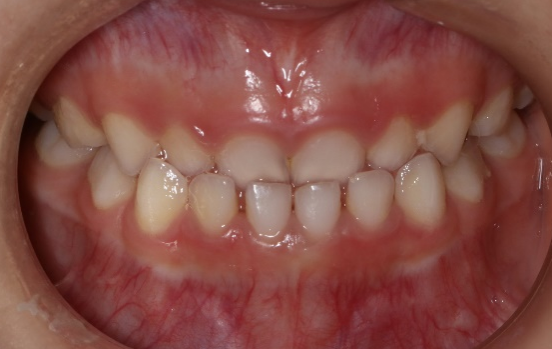

牙列拥挤

患者口腔内牙齿拥挤错位排列不齐,口腔内过于拥挤的牙齿发生牙周病及龋齿的概率比整齐的牙齿高出数倍。牙列拥挤不仅影响口腔问题,美学角度也大打折扣。